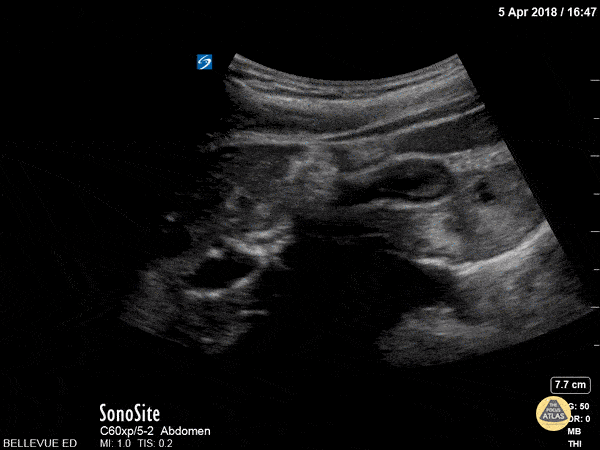

Biliary - Contracted Gallbladder

In this clip, the gallbladder (center right of the screen) appears collapsed and the wall looks thickened. This is the normal appearance of a postprandial gallbladder which is contracted because it has just released its bile content into the duodenum for digestion of a meal. Hannah Kopinksi and Dr. Lindsay Davis - NYU Emergency Medicine